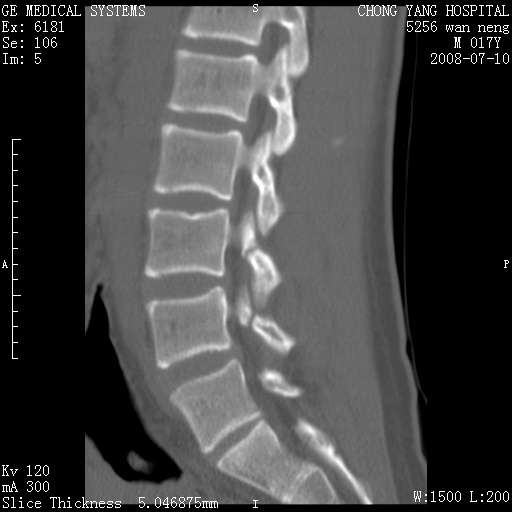

腰3、4椎弓崩裂

腰3、4椎弓不连

支持:腰3、4椎弓峡部崩裂。

腰3、4椎弓峡部不连

支持:腰3、4椎弓峡部崩解。

图片漂亮,目前也只能看到腰3、4骨质不连

腰3、4椎弓峡部裂。

重建图像见多个椎弓峡部不连(不足为据),平扫未见异常。

支持腰3、4椎弓峡部崩裂。